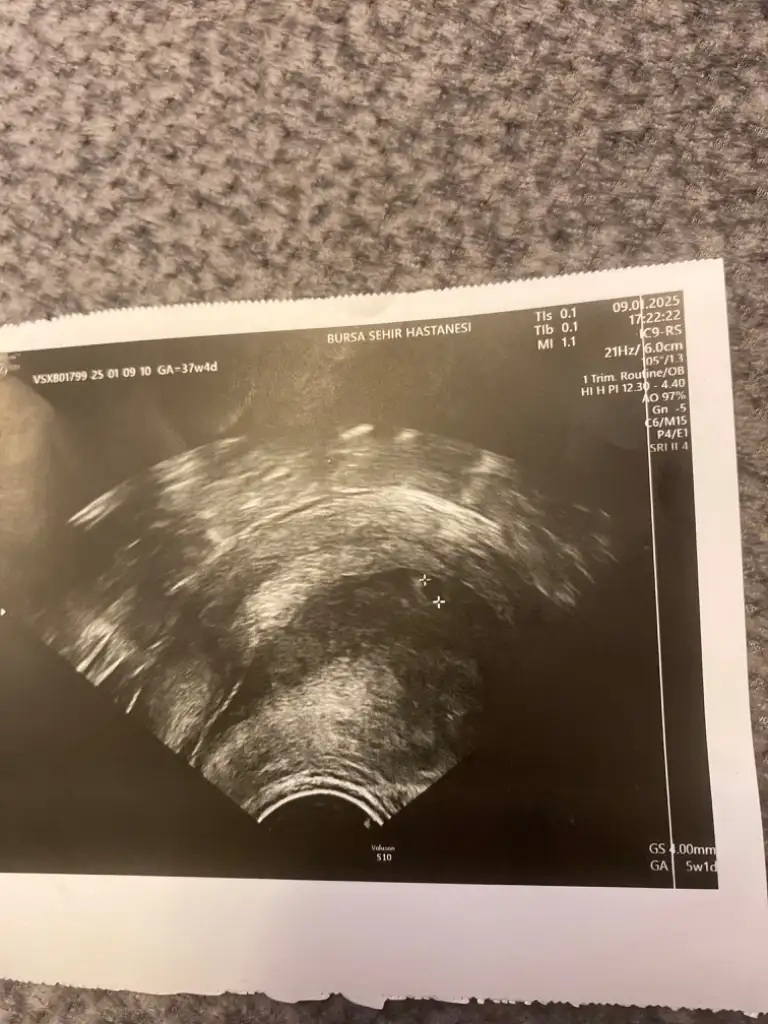

Canım merhaba tekrar doktora gittim bugün görünmez kese biz kist vs var mı ona bakalım derken kese göründü 🥰 Bilgin varsa yorumlayabilir misin yani kaç haftalık 4mm yazıyor acaba iyi mi ? Ben heyecandan doktora sormayı unuttum oda söylemedi başka hasta geldi falan 🙈

Hayırlı olsun canım 4 haftalık filan muhtemelen şuan 😊